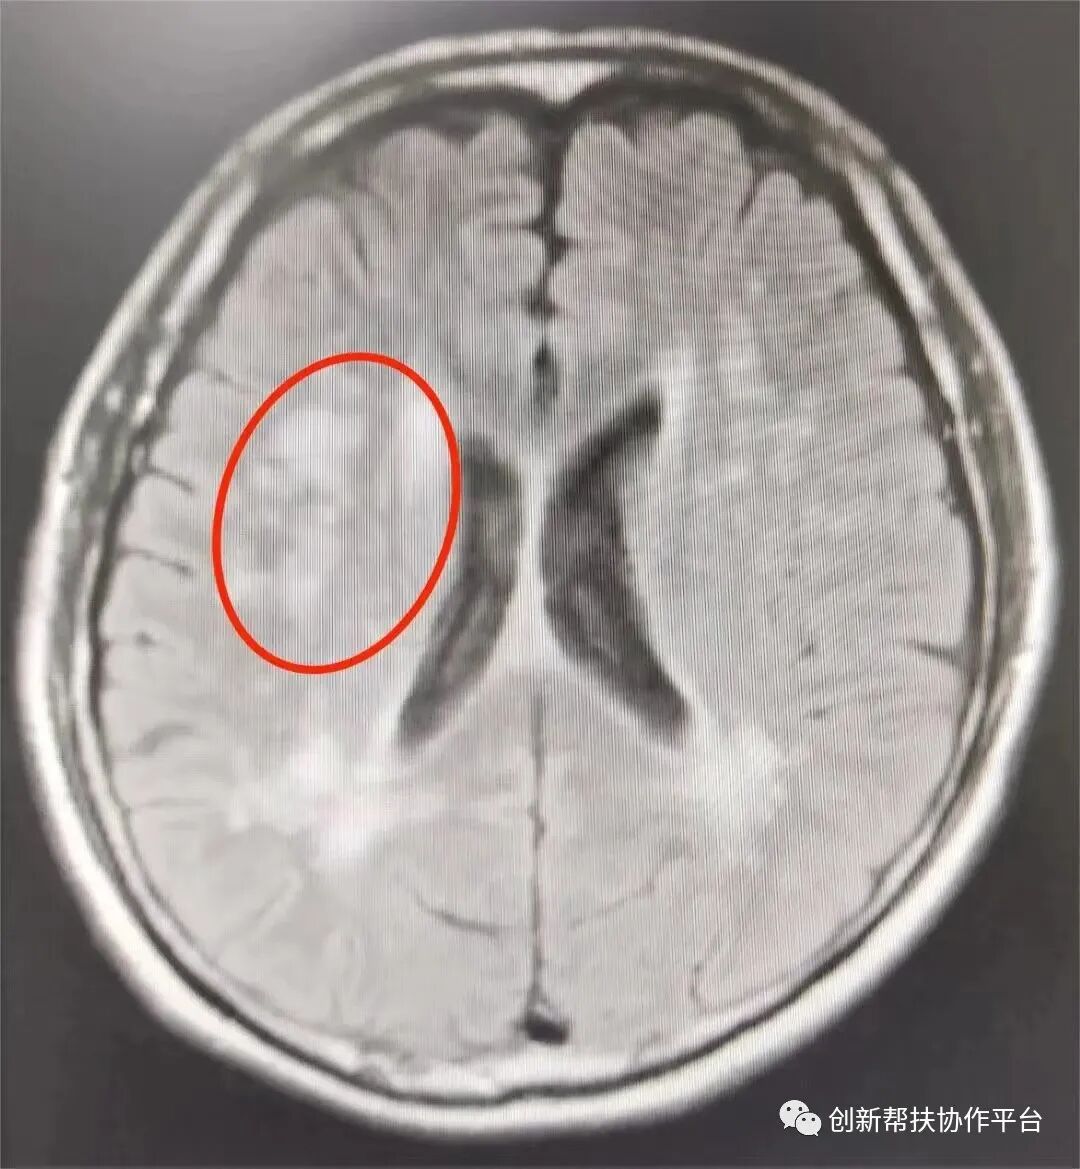

此前,张大爷来到遂宁一院神经内科就诊,主管医生协同神经内科给张大爷进行了肌电图、心电图、核磁共振等一系列检查,最后得出结论:“脑梗死确实存在,但是张大爷的一系列症状和脑梗死没有关系,怀疑是一种‘运动神经元疾病’”,但遂宁一院医疗技术、医师经验有限,无法确诊。

何教授与患者张大爷经过一个多小时充分沟通与交流,并现场指导检查,做出了进一步诊断,是“进行性延髓麻痹”。何教授还给出了康复建议,遂宁一院着手安排进一步的治疗训练,减轻张大爷的病痛。